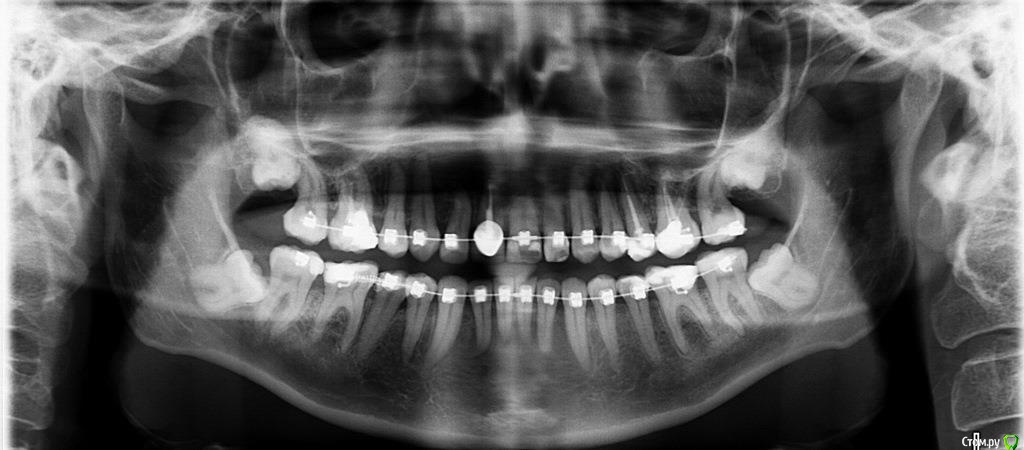

Galaola Опубликовано 28 февраля, 2016 Поделиться Опубликовано 28 февраля, 2016 Добрый день! Мне 36лет. Удалена правая верхняя 4 в детстве. При выборе ортодонта остановилась на варианте без удаления зубов, но с сепарацией зубов НЧ. Через 6 мес лечения ортодонт заявляет об удалении правой нижней 8 как минимум, а лучше всех. Прошу совета и мнения специалистов. Насколько необходимо удаление 8-к? Возможно ли расширить ВЧ и каким образом? Возможно ли подготовить место под имплант отсутствующей 4 или поставить адгезионный мост? Спасибо. Ссылка на комментарий

Brigita Опубликовано 9 марта, 2016 Поделиться Опубликовано 9 марта, 2016 8ки уже не прорежутся, их нужно удалять. Даже прорезанные зубы мудростм все 4 несут жевательную нагрузку около 3%, то есть они абсолютно в Вашем случае ненужные.Имплантация каких зубов планируется? Ссылка на комментарий